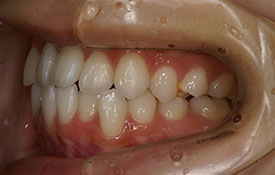

インビザラインの治療例:CASE-2

| プロフィール | 15歳 男性 |

| 所見 | アメリカから転院されて来られた方です。 インビザラインで上下顎の矯正治療を開始し下顎はアメリカで終了しており、上顎のみ治療の後期を担当しました。 アイライナーの装着は、1日平均22時間ほどでした。 |